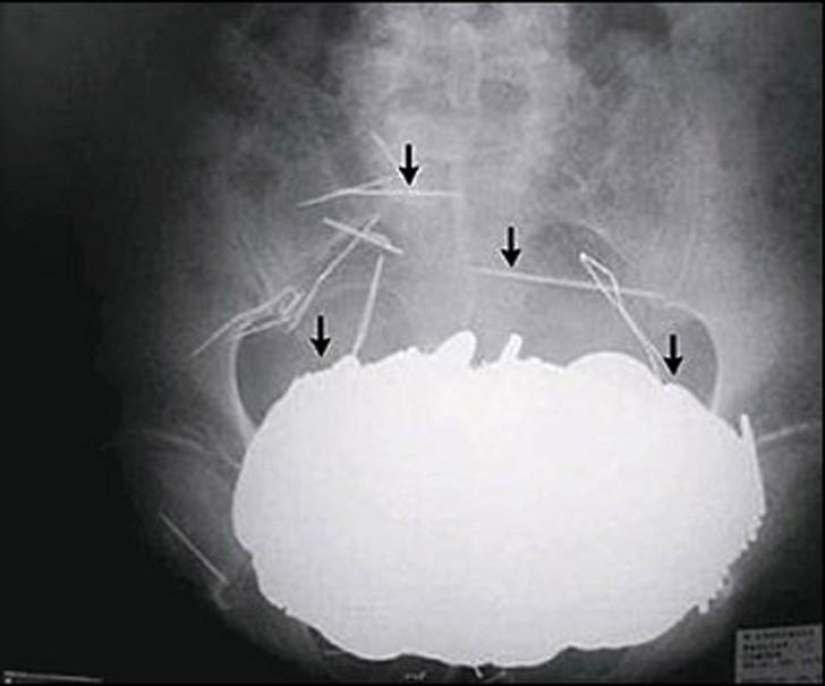

Tijeras.